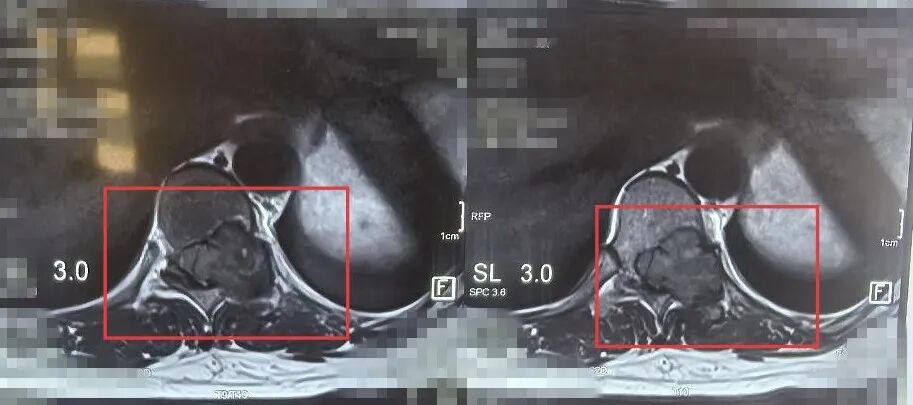

入院后,骨科团队为患者安排了全面细致的检查,最终确诊该患者为胸10椎体骨巨细胞瘤。这是一种具有侵袭性的良性肿瘤,发生在承担人体重量的核心椎体上,如同房屋的承重柱出现了问题,不仅导致剧烈疼痛,更随时有椎体病理性骨折、损伤脊髓神经导致瘫痪的风险。彻底切除肿瘤并重建脊柱的稳定性,是治疗的关键,但手术难度极高、风险极大。

面对挑战,刘邦定带领团队进行了多次深入的术前讨论。他们最终决定为患者施行目前脊柱肿瘤外科领域的前沿术式——“胸10椎体整块切除术” 。该技术旨在将肿瘤及其所在的椎体像一个“信封”一样完整取出,能最大程度降低肿瘤局部复发的几率。为了填补切除后留下的巨大“空缺”,团队采用了最先进的3D打印人工椎体”进行重建。